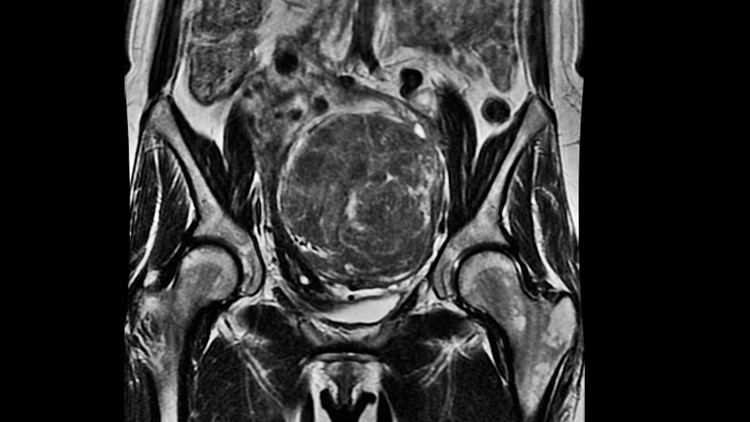

Kadın Hastalıkları, Doğum ve Jinekolojik Onkoloji Uzmanı Doç. Dr. İlker Kahramanoğlu, “Miyom, rahim düz kas dokusundan köken alan iyi huylu bir tümördür. Kişilerde çok sık görülmekle birlikte, özellikle üreme çağındaki kadınların neredeyse %50’sinde izlenmektedir.

Miyomlar çoğunlukla zararsız olup, tedavi gerektirmeyebilirler. Bununla beraber, boyut ve yerleşim yerlerine göre, bazı kadınlarda: adet düzensizliği, aşırı adet kanaması, tekrar eden alt karın ağrılarına yol açabilir. Daha nadiren, hamilelik planlayan kadınlarda, tekrarlayan düşük veya erken doğumla da ilişkili olabilir” dedi.

Kahramanoğlu,”Tüm dünya genelinde ve ülkemizde de, rahim alınması (histerektomi) ameliyatlarının en sık sebebi, miyomlardır. Bununla beraber, özellikle ileride gebe kalmayı planlayan veya herhangi bir sebeple rahmini aldırmak istemeyen kadınlarda, rahim korunarak miyomlar tedavi edilebilir” yorumunda bulundu.

‘Myomektomi’ olarak isimlendirilen bu ameliyatla, açık veya laparoskopik yani kapalı yöntemle, hastanın rahmi korunarak miyomlar çıkarılmaktadır. İlaçlara kıyasla miyomların tamamen kaybolması nedeniyle daha etkin bir yöntemdir diyebiliriz.